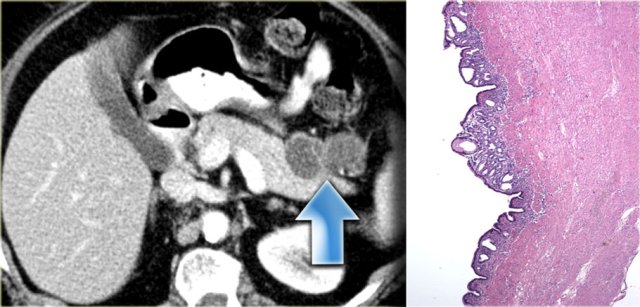

Enteric Duplication Cyst

Enteric duplication cyst is a cyst with a wall that has all three layers of the bowel wall, i.e. mucosa, submucosa and muscularis propria.

Although we commonly think of duplication cysts when we see a cystic mass adjacent to the bowel, we have to realize, that these are rare lesions.

They may occur anywhere in the mesentery, so either adjacent to or away from the bowel.

On the left an enteric duplication cyst.

It is located in the transverse mesocolon.

This patient was suspected of having a cystic pancreatic tumor.

The specimen demonstrates all the bowel wall layers.